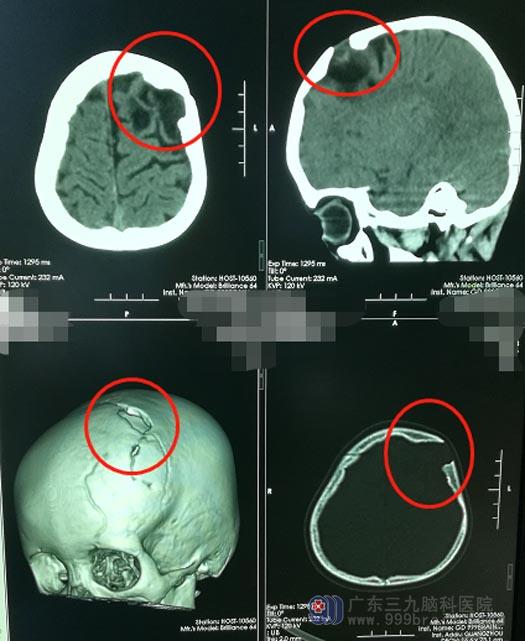

听了好友的介绍,他们带着鹏鹏来到了广东三九脑科医院神经外五科。查体时,医生发现鹏鹏左侧额部可触及一2.0cm×2.0cm大小的颅骨缺损、有搏动感。进一步头颅CT检查提示:1、额骨左侧局部骨质缺损,邻近左侧额叶软化灶形成并向外膨出,2、左侧额骨多发陈旧性骨折。主管医生结合鹏鹏之前的外伤史,考虑他是颅骨生长发育性骨折。